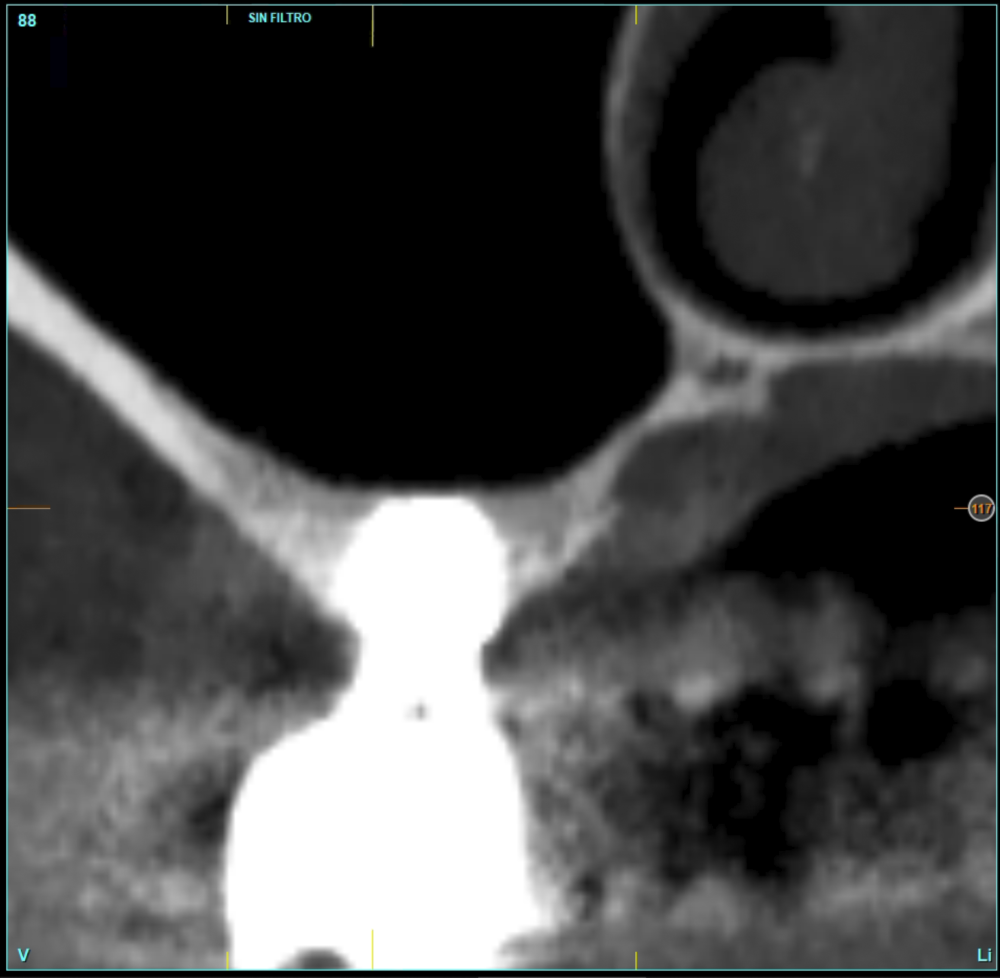

Material and method. A retrospective study has been carried out in patients in whom extra-short implants (4.5 and 5.5 mm length) were inserted directly by transcrestal elevation with residual ridges between 2 and 3 mm. The implant was the analysis unit for the descriptive statistics regarding location, implant dimensions, and radiographic measurements. The patient was the measurement unit for the analysis of age, sex and medical history. The main variable was the gain in height over the apex of the implant after 6 months of the surgery and one year after the load comparing both measurements and as secondary variables the biological complications and the implant failure were recorded.

Results. Ten patients who met the inclusion criteria were recruited and 20 implants were inserted. The mean residual bone volume height was 3.1 mm (+/- 0.3 mm with a range elevation above the apex of the implant in millimetres is of 2.8 mm (+/- 0.99 range 1.9 -5 mm). In the control cone-beam after one year of the studied load of the implants, the bone gain achieved was maintained, with no decrease in the volume gained, only three cases showed a decrease of between 0.4 and 0.5 mm of the initial volume at the end. No implants failed in the follow-up period and no biological complications were found in the surgery.

In this type of approach to the sinus, an important point is the stability of the grafted bone, located above the apex of the implant and with a bone tissue little vascularized (as usually occurs in these large atrophies with low density), so assessing what happens with the bone volume gained by this long-term procedure is also a key fact26,27. The mineralization of the bone graft and its maintenance once the implant loading is performed can make the difference in the success of the technique, especially in increasingly extreme cases. Therefore, the material used as a graft and the surface of the implant are two factors to take into account when performing this type of procedure28-31. Hydrophilic and osteoconductive surfaces in implants are of vital importance in these complex cases, as well as the filling materials that stimulate the formation of new bone28-31. The implants with UnicCa (Biotechnology Institute, Vitoria, Spain) surface, have a superhydrophilic surface. It is a very rough surface (Optima), with a calcium ions layer. This implies that the contact of blood and plasma with all points of the surface increases to the maximum the active surface for regeneration, by being completely coated with fluids due to its high capillarity. In the following series of clinical cases, patients treated by transcrestal sinus lift, with extra-short and ultra-short implants (4.5 and 5.5 mm), BTI (Biotechnology institute), of internal connection and universal plus platform in residual bone heights below 3 mm, studying the behaviour of implants regarding their survival as well as the maintenance of the bone volume achieved in the crestal elevation.